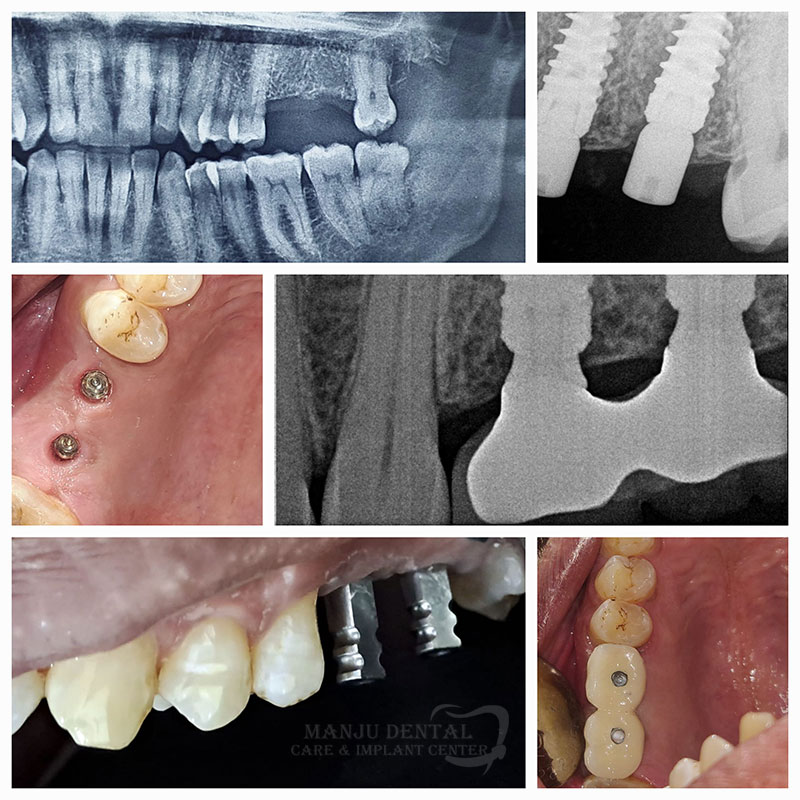

Our Gallery

Dental implant the gold standard for tooth replacement

Osteointegrated implant achieving perfect function and form

Full Spectrum Dental Care Extraction of Non Restorable Tooth, Implant Placement and Re-Rct of Adjacent Tooth

Precise Implant Placement For Long Term Stability And Natural Esthetics